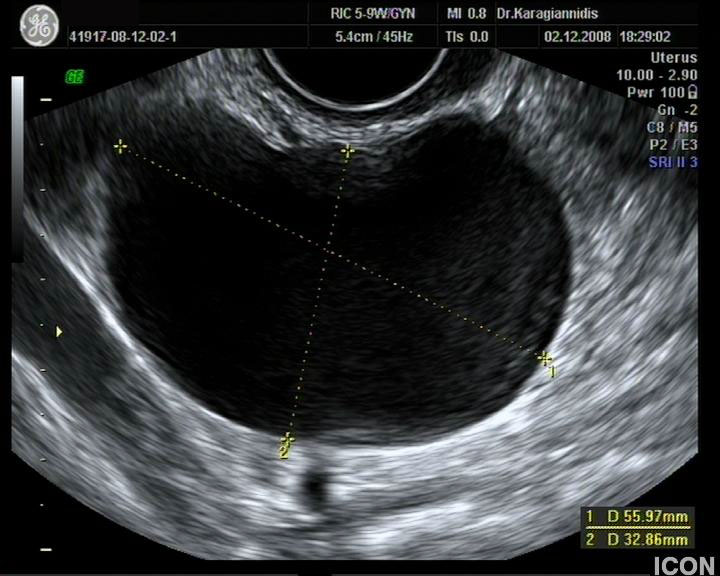

Ενδοκολπικός U/S έσω Γεννητικών Οργάνων